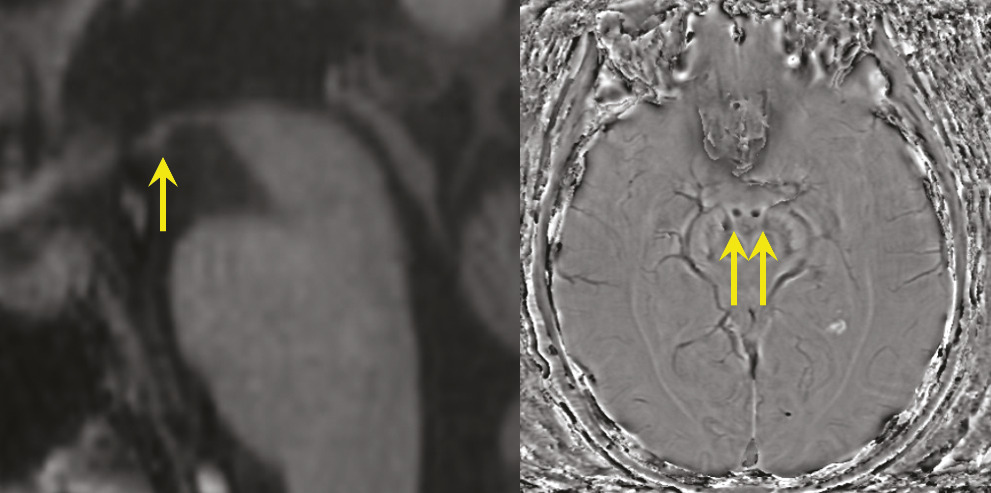

Syndrome de Korsakoff, lié à une carence en vitamine B1

Décrit initialement en 1881 chez des alcooliques, en association avec une polyneuropathie, l’origine du syndrome de Korsakoff est éthylo-carentielle. Depuis lors, d’autres causes carentielles ont été identifiées, parmi lesquelles l’hyperémèse gravidique (vomissements incoercibles du premier trimestre de la grossesse) ou les complications de la chirurgie bariatrique. Leur point commun est la carence en vitamine B1, à l’origine d’une nécrose hémorragique des corps mamillaires (fig. 4) et/ou des lésions des noyaux antérieurs et dorso-médians du thalamus,4 qui interrompent de façon bilatérale le circuit de Papez (voir l’article « Anatomie de la mémoire » page 1072 ).